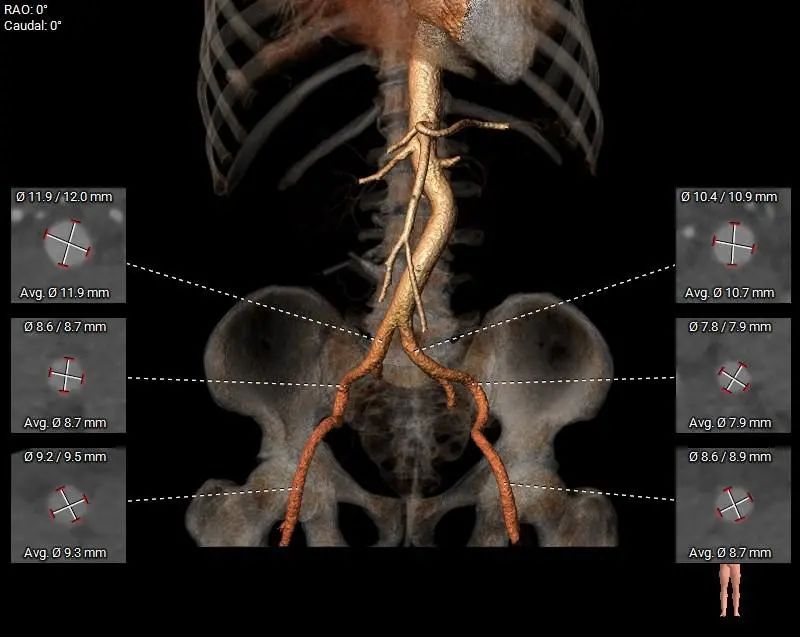

主动脉根部测量

瓣上结构测量

冠脉阻挡风险、左室大小及横位心评估

外周血管入路评估

Type-1型二叶式主动脉瓣,瓣叶重度钙化并增厚,钙化主要分布在瓣叶及管壁附着缘上;

左右冠开口高度可,双侧冠脉切线位瓣叶长度<冠脉开口上缘到瓣叶附着缘距离,无明显钙化分布;

左室心腔内径增大,LVOT呈敞口状,瓦氏窦内径和升主动脉内径增宽,窦管交界内径可;

主动脉瓣环水平夹角60°,横位心,主动脉弓角度及弓距可;

入路血管走形稍迂曲,无明显钙化分布,血管内径可。